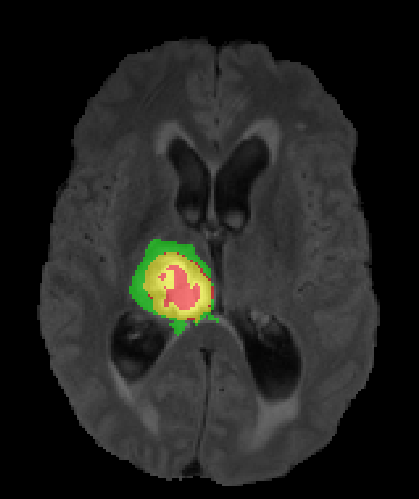

We argue that the sub-optimal paradigm of processing different abstractions within a single CNN pipeline can be remedied through the effective processing of information in a structured manner. Consequently, we devise strategies for disentangling the edge and texture information within a single training pipeline. Figure 2 illustrates how our proposed module, dubbed EG-CNN, can be paired with any existing CNN encoder-decoder to improve segmentation quality near intensity edges. We have applied our EG-CNN to the tasks of brain and liver tumor segmentation in medical images (Figure 3).

Edge-Aware 2D Image Segmentation Networks

[49; 48]: Fully convolutional neural networks (CNNs) have proven to be effective at representing and classifying textural information, thus transforming image intensity into output class masks that achieve semantic image segmentation. In medical image analysis, however, expert manual segmentation often relies on the boundaries of anatomical structures of interest. We propose 2D edge-aware CNNs for medical image segmentation. Our networks are designed to account for organ boundary information, both by providing a special network edge branch and edge-aware loss terms, and they are trainable end-to-end. We validate their effectiveness on the task of brain tumor segmentation using the BraTS 2018 dataset. Our experiments reveal that our approach yields more accurate segmentation results, which makes it promising for more extensive application to medical image segmentation. -

3.

Plug-and-Play Edge-gated 3D Image Segmentation Networks

[50]: We propose a plug-and-play module, dubbed Edge-Gated CNNs (EG-CNNs), that can be used with existing encoder-decoder architectures to process both edge and texture information. The EG-CNN learns to emphasize the edges in the encoder, to predict crisp boundaries by an auxiliary edge supervision, and to fuse its output with the original CNN output. We evaluate the effectiveness of the EG-CNN against various mainstream CNNs on the publicly available BraTS19 dataset for brain tumor semantic segmentation, and demonstrate how the addition of EG-CNN consistently improves segmentation accuracy and generalization performance. -